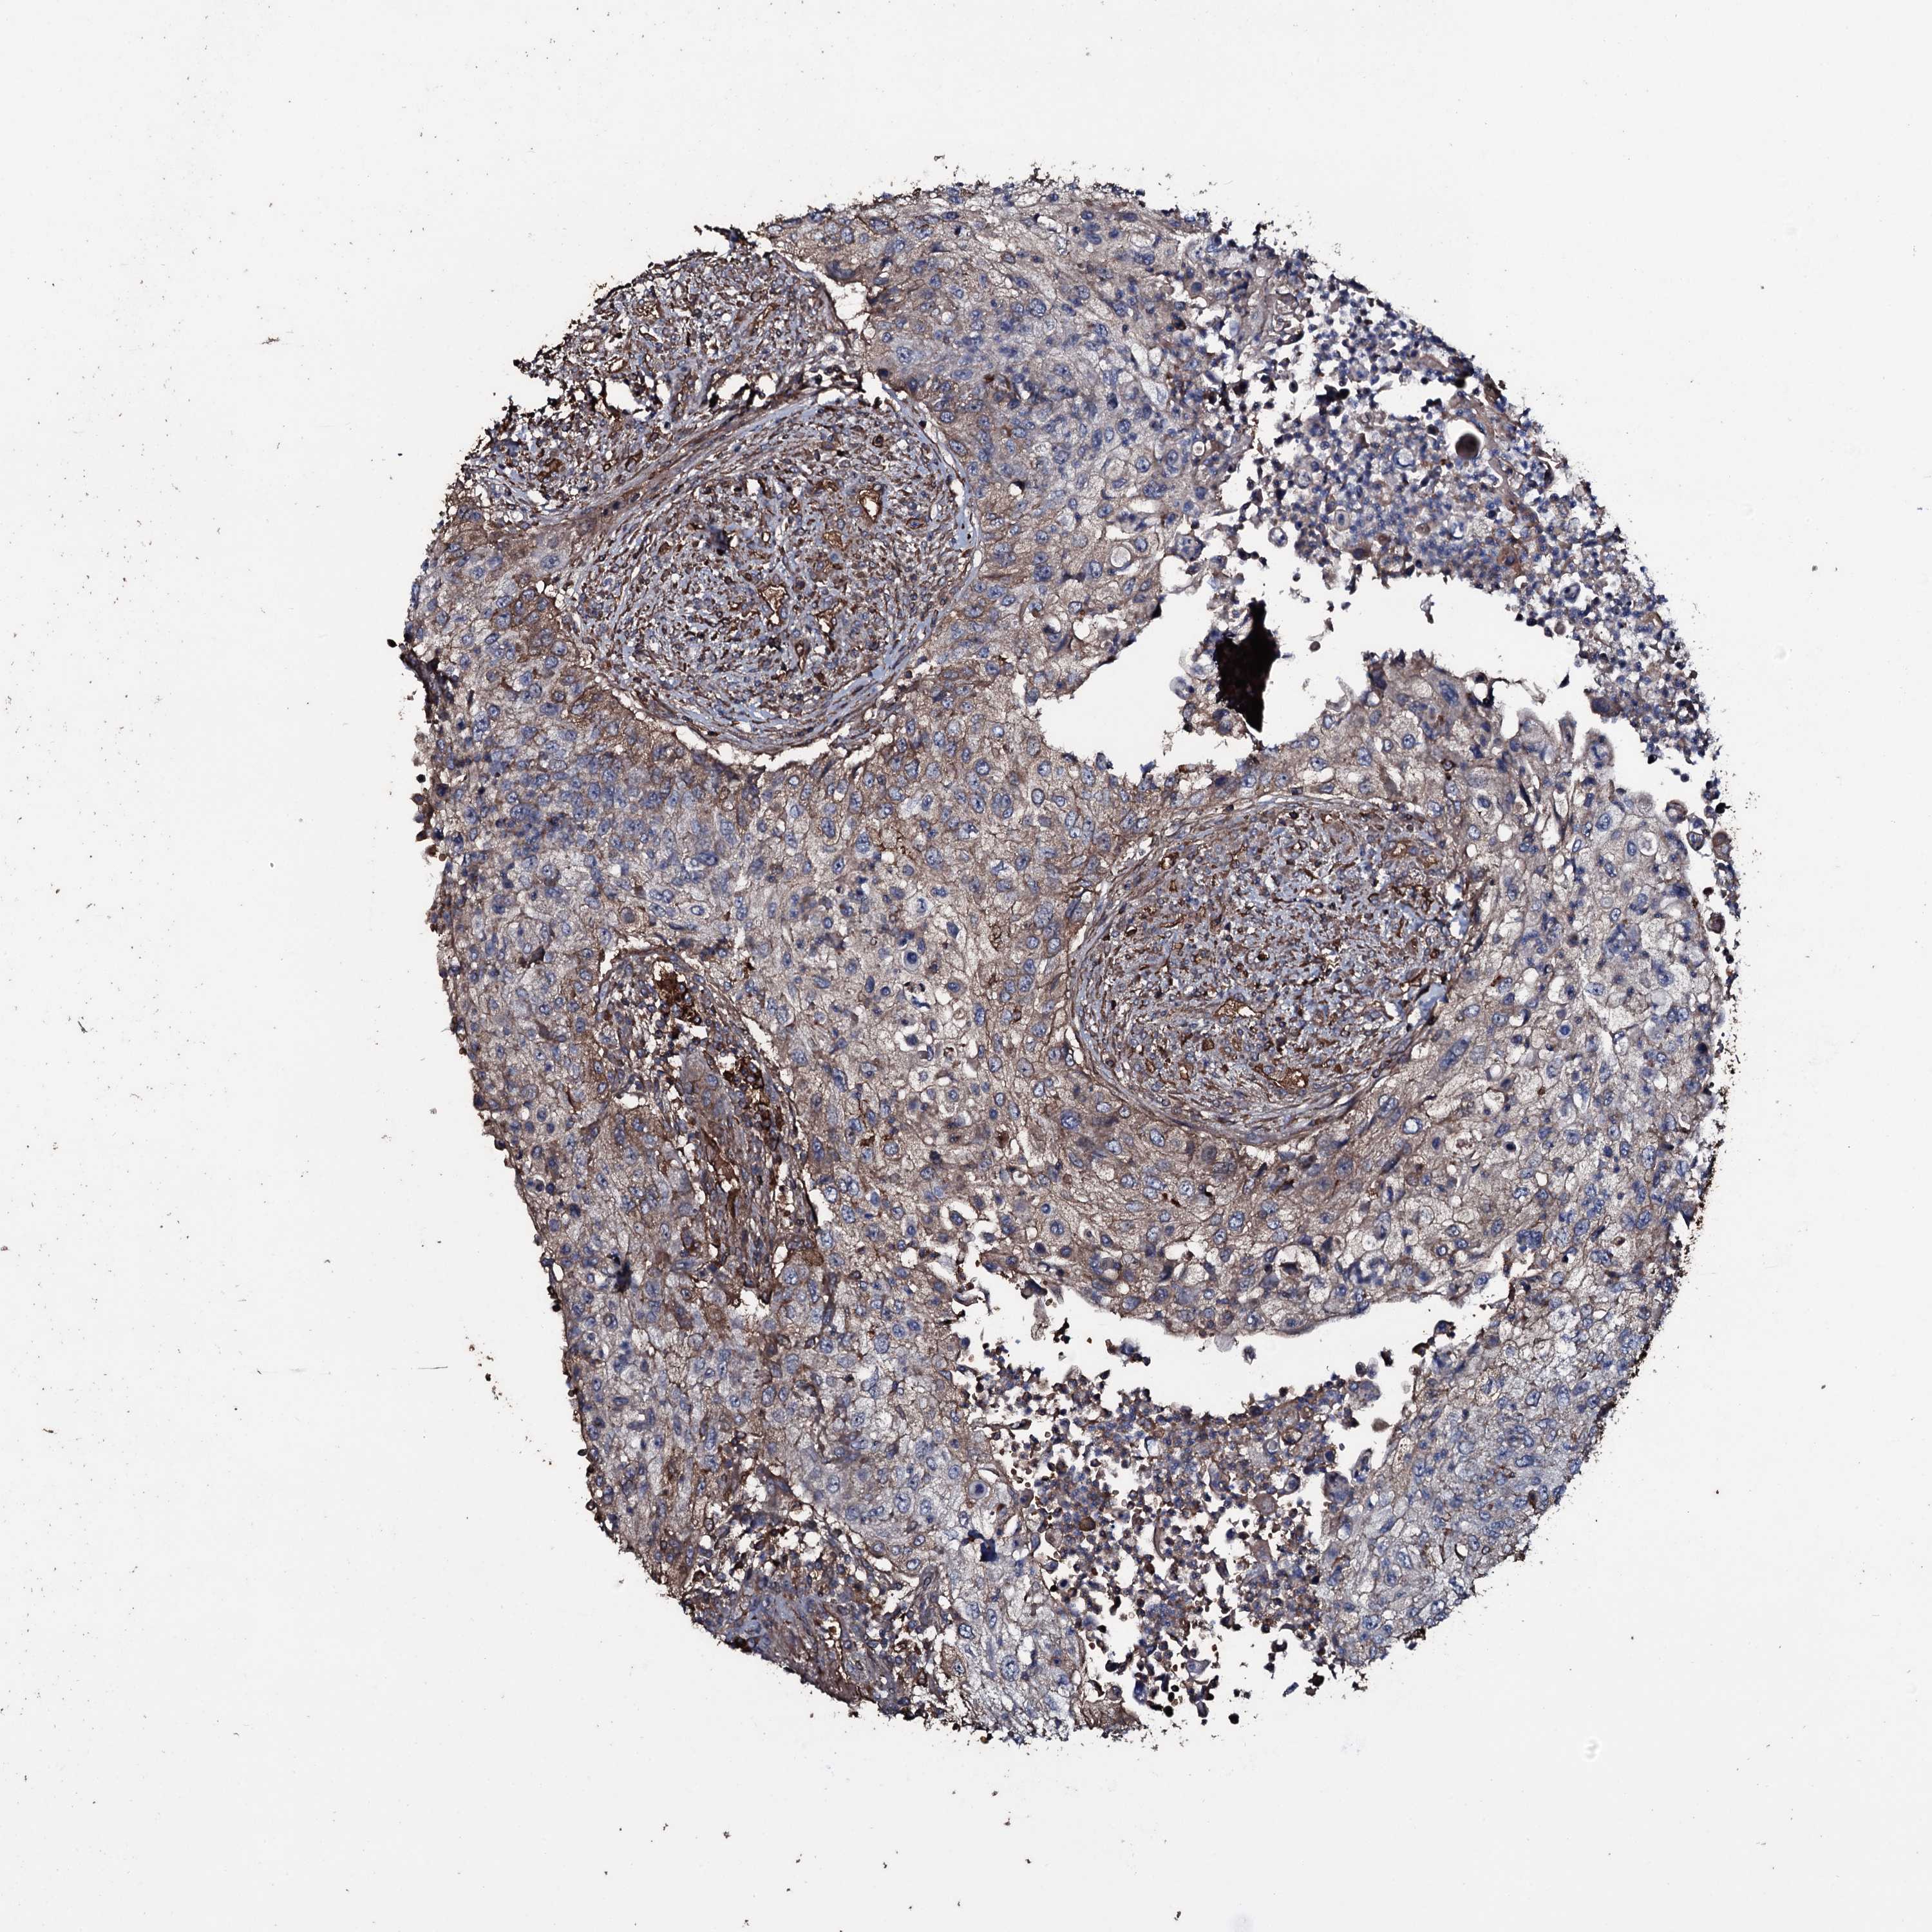

UROTHELIAL CANCER - Protein expressioni

A mouse-over function shows sample information and annotation data. Click on an image to view it in a full screen mode. Samples can be filtered based on level of antibody staining by selecting one or several of the following categories: high, medium, low and not detected. The assay and annotation is described here.

Antibody stainingi

Antibody staining in the annotated cell types in the current human tissue is reported as not detected, low, medium, or high, based on conventional immunohistochemistry profiling in selected tissues. This score is based on the combination of the staining intensity and fraction of stained cells.

Each image is clickable and will lead to virtual microscopy that enables deeper exploration of all samples and also displays staining intensity scores, fraction scores and subcellular localization as well as patient and tissue information for each sample.

Antibody HPA041244

Staining

High

Medium

Low

Not detected

Intensity

Strong

Moderate

Weak

Negative

Quantity

>75%

75%-25%

<25%

None

Location

Nuclear

Cytoplasmic/membranous

Cytoplasmic/membranous,nuclear

Urothelial carcinoma, High grade

Urothelial carcinoma, Low grade